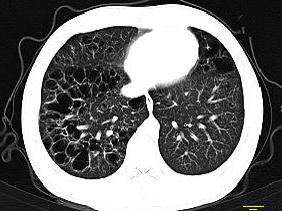

问题 男,3岁,活动气喘,查体压头颅骨有乒乓球感,肝脾大,根据影像学检查图像,最可能的诊断为 ( )

选项 A.肺间质纤维化 B.组织细胞增生症 C.先天性支气管扩张 D.先天性肺囊肿 E.肺发育不良

答案 B